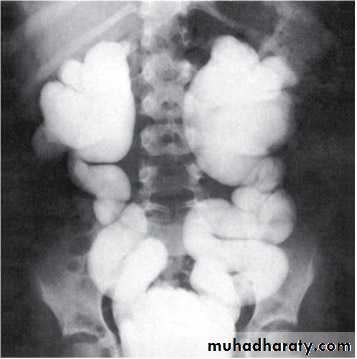

Grading of VUR

The degree of reflux is graded I–V.

Grading is based on the appearance of contrast agent in the collecting system during voiding cystourethrography (VCUG(.

The VCUG:

the definitive examination

to diagnose and grade reflux and establish reversible causes

must include a voiding phase:

in some cases, reflux may be seen only during the elevated intravesical pressures associated with micturition.

in visualizing the urethra, may allow the diagnosis of outflow obstruction to be made (e.g., posterior urethral valves).

MCUG